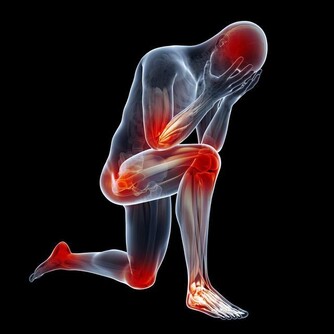

風濕疾病的患者,平時要注意盡量不要吃海產品,應該要多吃綠色的蔬菜水果,並且要適當攝入鈣元素,可以有效避免骨質疏鬆,平時也需要加強鍛煉,適當鍛煉身體,可以增強骨骼的堅硬度,可以避免骨質疏鬆,而且可以有效緩解關節疼痛,風濕病的四大飲食禁忌。

風濕病患者在雨季可多食蘿蔔、米仁、芡實、玉米、扁豆等化濕的食品,可改善病情。此外,風濕病大多侵害骨關節,而中醫以為,腎主骨,多吃芝麻、核桃等補腎食品對風濕病也有利。

脂肪在體內氧化過程中,能產生酮體,而過多的酮體,對關節有較強的刺激作用,故患者不宜多吃高脂肪類食物,如牛奶、肥肉等,炒菜、燒湯也宜少放油。

病人不宜多吃海產品,如海帶、海參、海魚、海蝦等,因其中含有尿酸,被人體吸收後,能在關節中形成尿酸鹽結晶,使關節症狀加重。